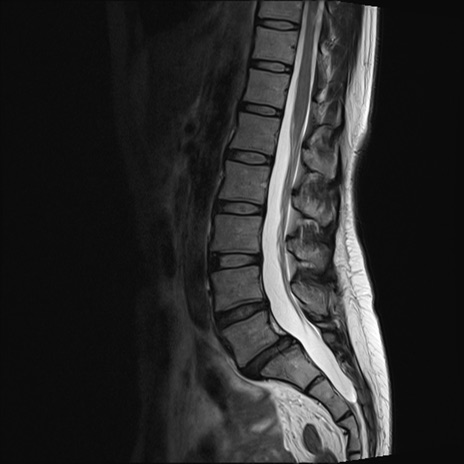

【整形】TIPS症例4 腰椎MRI T2WI(矢状断像)

腰椎MRI

T1WI(矢状断像)